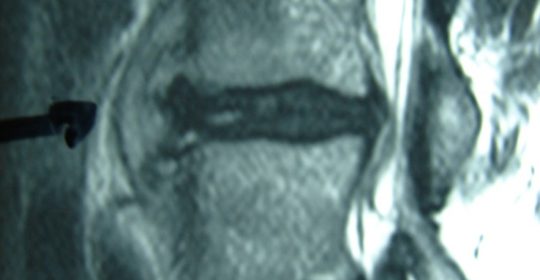

Μαγνητική Τομογραφία της Ο.Μ.Σ.Σ. (13/06/2007) Ακολουθία Τ1 και Τ2

Οβελιαία τομή (α,β) Παρατηρείται η ύπαρξη Επισκληριδίου Αποστήματος στο επίπεδο Ο3-Ο4 που προκαλεί μεγάλη στένωση του σπονδυλικού σωλήνα, με απώθηση του νωτιαίου σάκου. Διαπιστώνεται επίσης η ύπαρξη παρα-σπονδυλικού αποστήματος

Εγκαρσία τομή (γ,δ) Παρατηρείται η ύπαρξη Επισκληριδίου όπως επίσης και προ-παρασπονδυλικού αποστήματος.